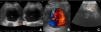

La angiografía computarizada multifásica (angio-TC) es de elección en situaciones de urgencia, permitiendo una evaluación detallada de las estructuras vasculares. La resonancia magnética, la ecografía y las técnicas de medicina nuclear pueden ser útiles en ciertos casos.

Multiphasic computed tomography angiography (CTA) is the gold standard in emergency situations, enabling a detailed evaluation of vascular structures. Magnetic resonance imaging, ultrasound and nuclear medicine techniques may be useful in certain cases.